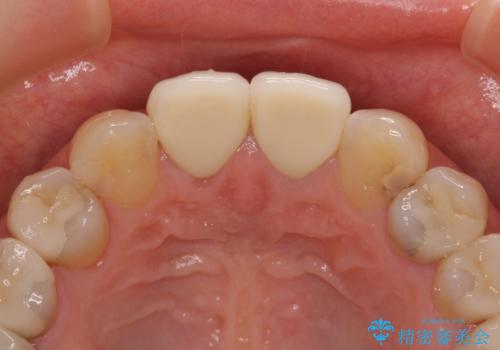

- 上顎2前歯の色を気にして来院された患者様です。

2本ともに虫歯治療による充填材の変色などによりつぎはぎのような前歯となっていたため、オールセラミッククラウンにて補綴治療を行うこととしました。